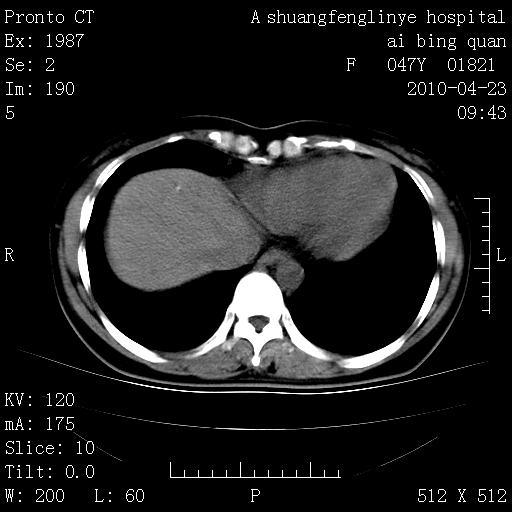

标题: CT25944:胸痛、气短、前几日高烧!肺Ca?请会诊! [打印本页]

标题: CT25944:胸痛、气短、前几日高烧!肺Ca?请会诊!

kaolv 周围型肺癌并同肺转移

双肺多发结节,考虑转移瘤,肺癌肺转移不除外

周围型肺癌并肺转移

左侧乳腺低密度灶

双肺多发结节,部分密度较高,最大结节边缘光滑。临床有“胸痛、气短、前几日高烧”病史。首选考虑:右肺感染性病变!建议积极消炎后复查!